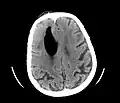

CT scans of patients with a tension pneumocephalus typically show air that compresses the frontal lobes of the brain, which results in a tented appearance of the brain in the skull known as the Mount Fuji sign.[1][2][3] The name is derived from the resemblance of the brain to Mount Fuji in Japan, a volcano known for its symmetrical cone. In typical cases, there is a symmetrical depression near the midline (such as the crater of a volcano), due to intact bridging veins.[3] Its occurrence seems to be limited to tension pneumocephalus (not occurring in pneumocephalus without tension).[4] The sign was first described by a team of Japanese neurosurgeons.[5]

Large pneumocephaly secondary to surgical wound

Pneumocephaly